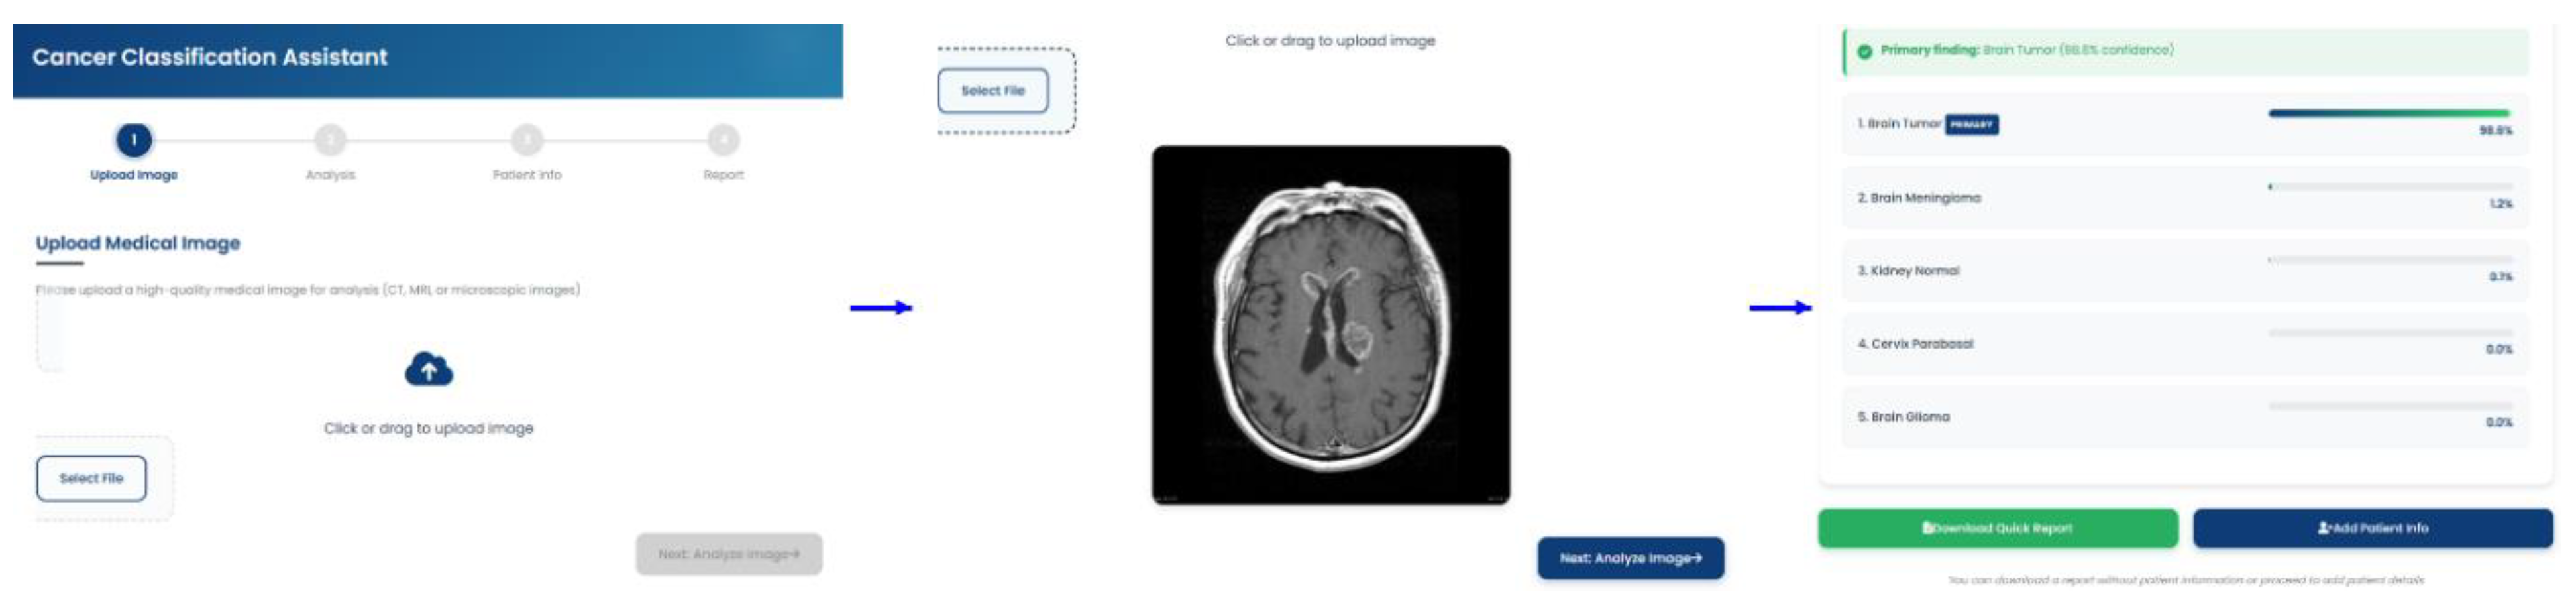

3.5. Performance of the Deployed Web-Based Tool